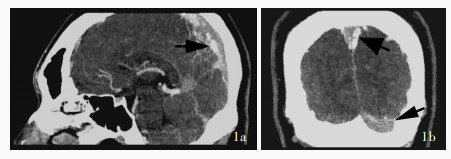

Zhang M , Shi B , Zhao M . Cerebral venous thrombosis with hyperhomocysteinemia due to loss of heterozygosity at methylenetetrahydrofolate reductase (MTHFR) locus: a case report. BMC Neurol, 2023, 23: 154.